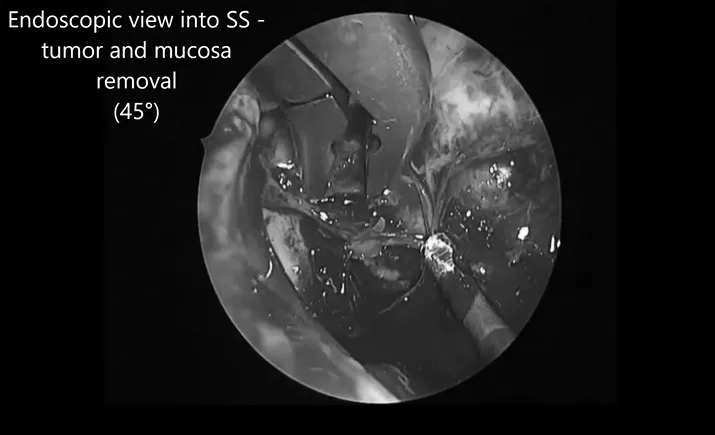

▼内镜辅助阶段

显微手术切除肿瘤后,内镜辅助下切除在蝶窦内的肿瘤残体和粘膜。应用自体脂肪和纤维蛋白胶对硬脑膜进行水密封闭。